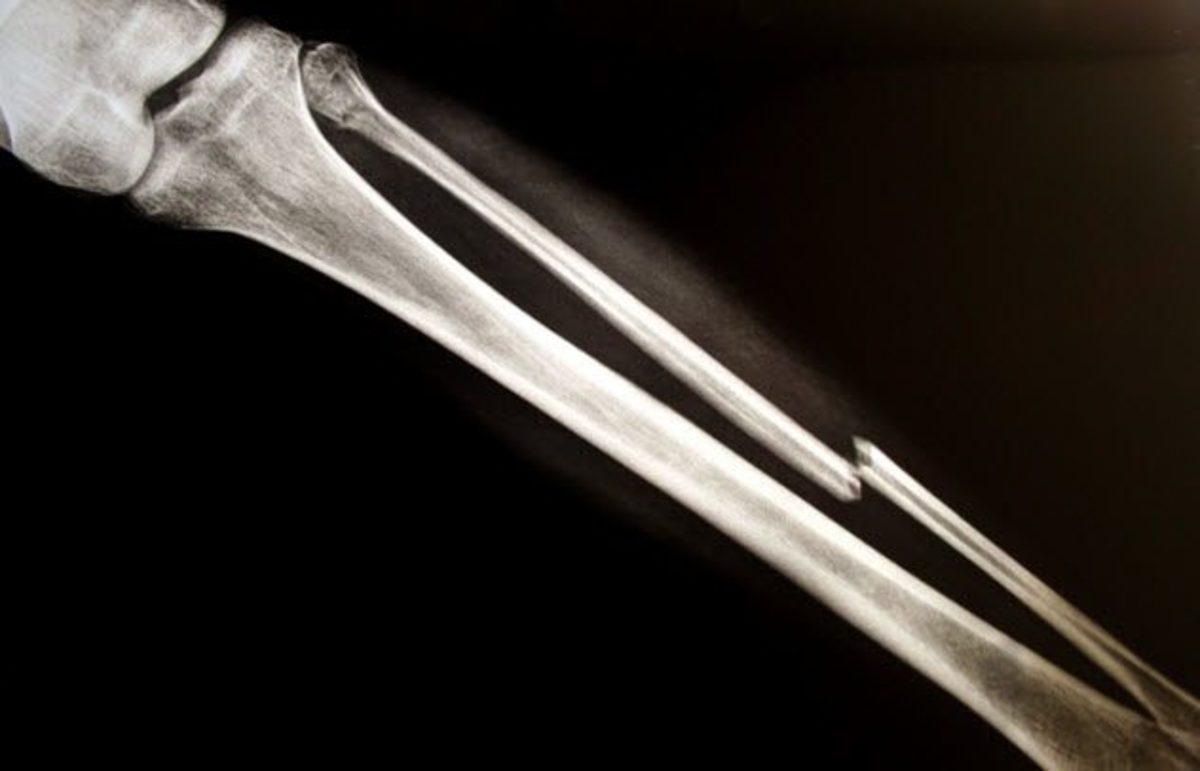

Kemik, Kas ve Sinir Rejenerasyonu ve Kemik Transplantasyon Deneyleri:

Yaklaşık bir yıl boyunca; kemikleri, kasları ve sinirleri yeniden üretmek için Ravensbruck toplama kampındaki esirler üzerinde deneyler yapıldı. Sinir operasyonlarıyla esirlerin sinir uzuvları canlı canlı çekildi. Bazılarının kemikleri kırıldı ve rejenerasyon deneyleri yapıldı. İddialara göre kemik nakli için kapsamlı operasyonlar gerçekleştirildi.